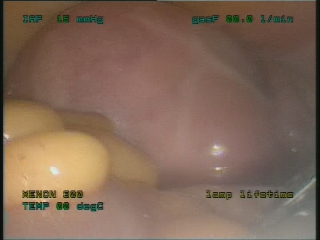

Η θεραπεία της αδενομύωσης εξαρτάται από την έκταση της βλάβης, την ηλικία της γυναίκας και την επιθυμία της να τεκνοποιήσει. Συντηρητικά: Αντισυλληπτικά δισκία, GnRH ανάλογα, προγεσταγόνο σε συνεχή χορήγηση, μη στεροειδή αντιφλεγμονώδη, χρήση φαρμακευτικού ενδομητρίου σπειράματος Χειρουργικά: Με τη Λαπαροσκοπική αδενομυωματεκτομή αντιμετωπίζονται τα αδενομυώματα κυρίως στην αναπαραγωγική ηλικία οπότε και η γυναίκα επιθυμεί τη διατήρηση της γονιμότητάς της. Επίσης σε περίπτωση που απαιτηθεί ολική υστερεκτομή και αυτή πραγματοποιείται λαπαροσκοπικά.